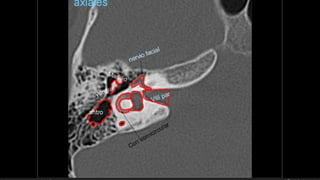

Evaluación Imagenologica

• #38 Izqu. AXIAL-- fxLongitudinal perdonan la capsula otica (laberinto oseo) Centro AXIAL fx trnasversa lascuales tperdonan el lab erinto oseo Dere: MIXTA – tmp perdona

• #51 IZQ: Canal arqueado(petromastoideo) . Canal SC superior DER: Hiato del facial(blanca), ganglio geniculado (negra)